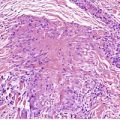

Inflammatory lesions have traditionally been attributed to the accumulation of neutrophils within microcomedones or comedones with subsequent rupture of the follicle and the formation of a pustule in the dermis. It now appears that there is an even earlier stage which involves the transmigration of lymphocytes into the wall of the follicle associated with increasing spongiosis of the follicular epithelium (Fig. 15.1). 171 This change has been likened to an allergic contact sensitivity reaction. 171 This is followed after 24–72 hours by the accumulation of neutrophils within the follicle, leading to its distension and subsequent rupture. 171 There may be a localized loss of the granular layer in the region of the eventual rupture, suggesting a defect in keratinization in this region. A perifollicular pustule develops following the rupture of the comedo (Fig. 15.2). Lymphocytes, plasma cells, and foreign body giant cells subsequently appear. The follicular epithelium tends to encapsulate the inflammatory mass; sometimes this is followed by the formation of draining sinuses lined by remnants of the follicular epithelium. When the inflammatory process subsides, distorted secondary comedones may result.

Acne vulgaris (early lesion). There is transmigration of lymphocytes through the spongiotic epithelium lining a microcomedone. A few neutrophils are present along the inner edge. (H & E)